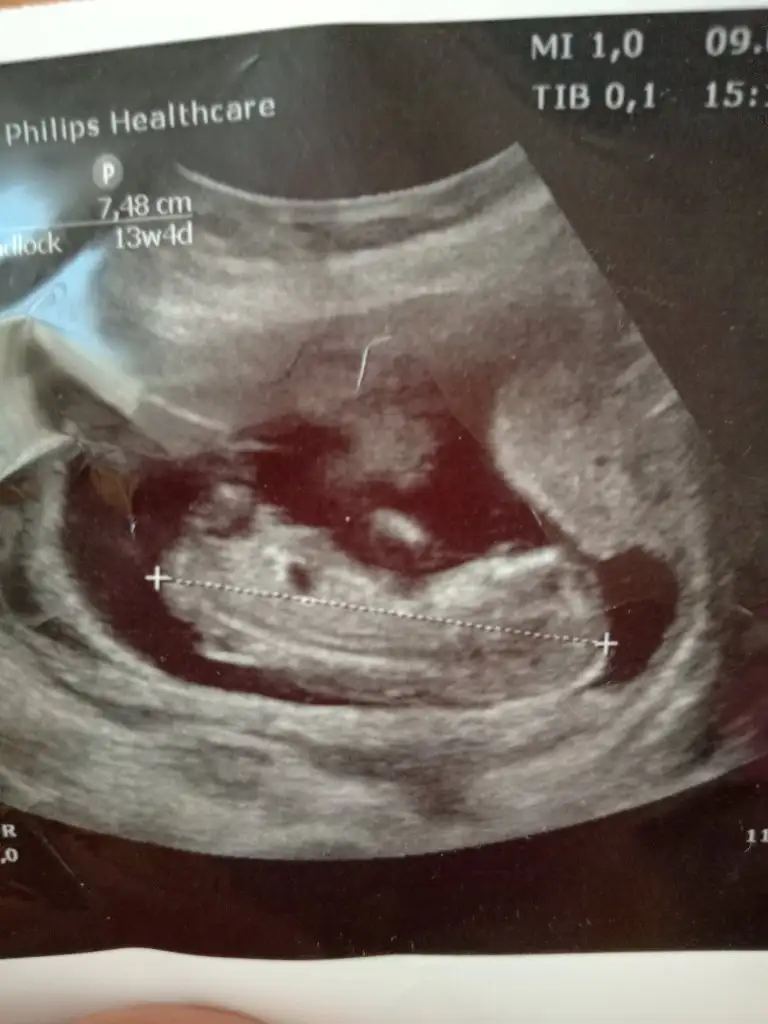

Kaç haftalık sanki erkek gibi geldi başka usg varsa paylaşın az yan pozisyonda minnoşEki Görüntüle 2662857 arkadaşlar merhaba benim ufaklık ta göstermedi Bi türlü tahminlerinizi alabilirmiyim acaba çok merak ediyorum![]()

Atın bakim ama en iyi 11 12 13 haftalar10+3 atsam bakabilir misiniz

12 de tekrar gidicem o zamanda atarım merakıma yenildimAtın bakim ama en iyi 11 12 13 haftalar![]()

Hayırlısı bakalımKaç haftalık sanki erkek gibi geldi başka usg varsa paylaşın az yan pozisyonda minnoş![]()